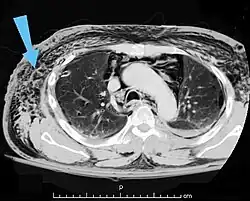

| An abdominal CT scan of a patient with subcutaneous emphysema (arrows) | |

Significant cases of subcutaneous emphysema are easy to diagnose because of the characteristic signs of the condition.[1] In some cases, the signs are subtle, making diagnosis more difficult.[13] Medical imaging is used to diagnose the condition or confirm a diagnosis made using clinical signs. On a chest radiograph, subcutaneous emphysema may be seen as radiolucent striations in the pattern expected from the pectoralis major muscle group. Air in the subcutaneous tissues may interfere with radiography of the chest, potentially obscuring serious conditions such as pneumothorax.[18] It can also reduce the effectiveness of chest ultrasound.[28] On the other hand, since subcutaneous emphysema may become apparent in chest X-rays before a pneumothorax does, its presence may be used to infer that of the latter injury.[13] Subcutaneous emphysema can also be seen in CT scans, with the air pockets appearing as dark areas. CT scanning is so sensitive that it commonly makes it possible to find the exact spot from which air is entering the soft tissues.[13] In 1944, M.T. Macklin and C.C. Macklin published further insights into the pathophysiology of spontaneous Macklin's Syndrome occurring as a result of a severe asthmatic attack.